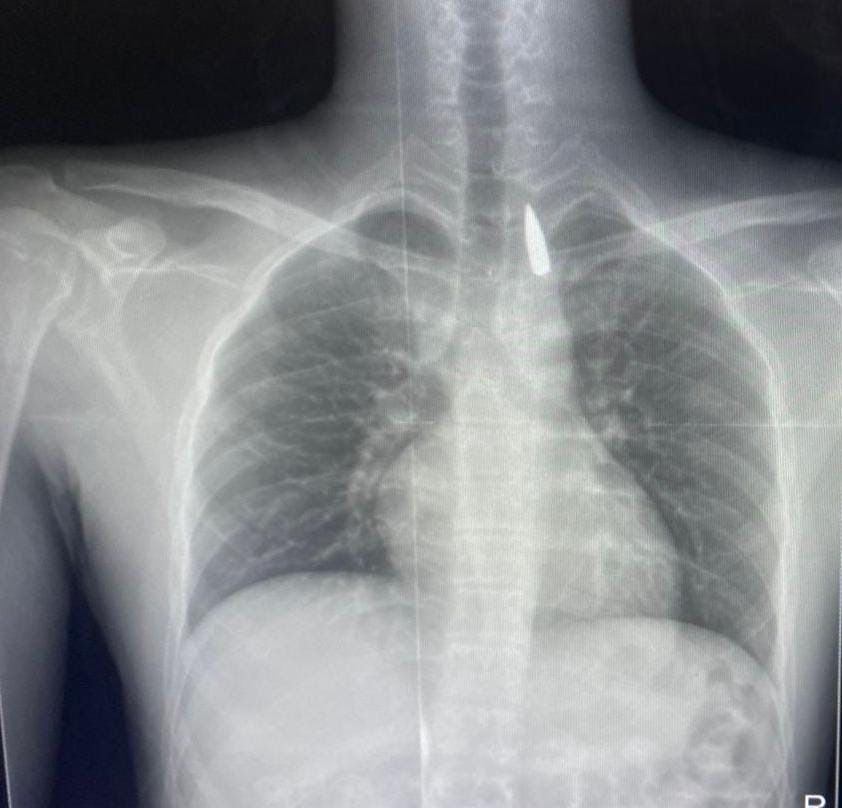

وأوضح الدكتور تامر عبد الله، عميد كلية الطب ورئيس مجلس إدارة المستشفيات الجامعية، أنه في يوم 21 أكتوبر 2025 تمكن فريق من أطباء قسم جراحة القلب والصدر والتخدير والمعاونين من إجراء جراحة دقيقة بالغة الخطورة لأحد المرضى المحجوزين من قطاع غزة، والذي كان قد تعرض لإصابة بطلق ناري في الرأس منذ فترة، استقر المقذوف على إثرها داخل تجويف القفص الصدري قرب الشريان الأورطي، وهو أكبر وأهم شرايين الجسم والمسؤول عن تغذية جميع الأعضاء الحيوية.

وأضاف أن الفريق الطبي، رغم دقة الحالة وتعقيدها، نجح في استخراج المقذوف بأمان بعد عملية جراحية نادرة استمرت عدة ساعات داخل المستشفى الجامعي الجديد، حيث خضع المريض بعدها للرعاية الطبية اللازمة، وحالته حاليًا مستقرة وتحت المتابعة الدقيقة من الفريق المختص.